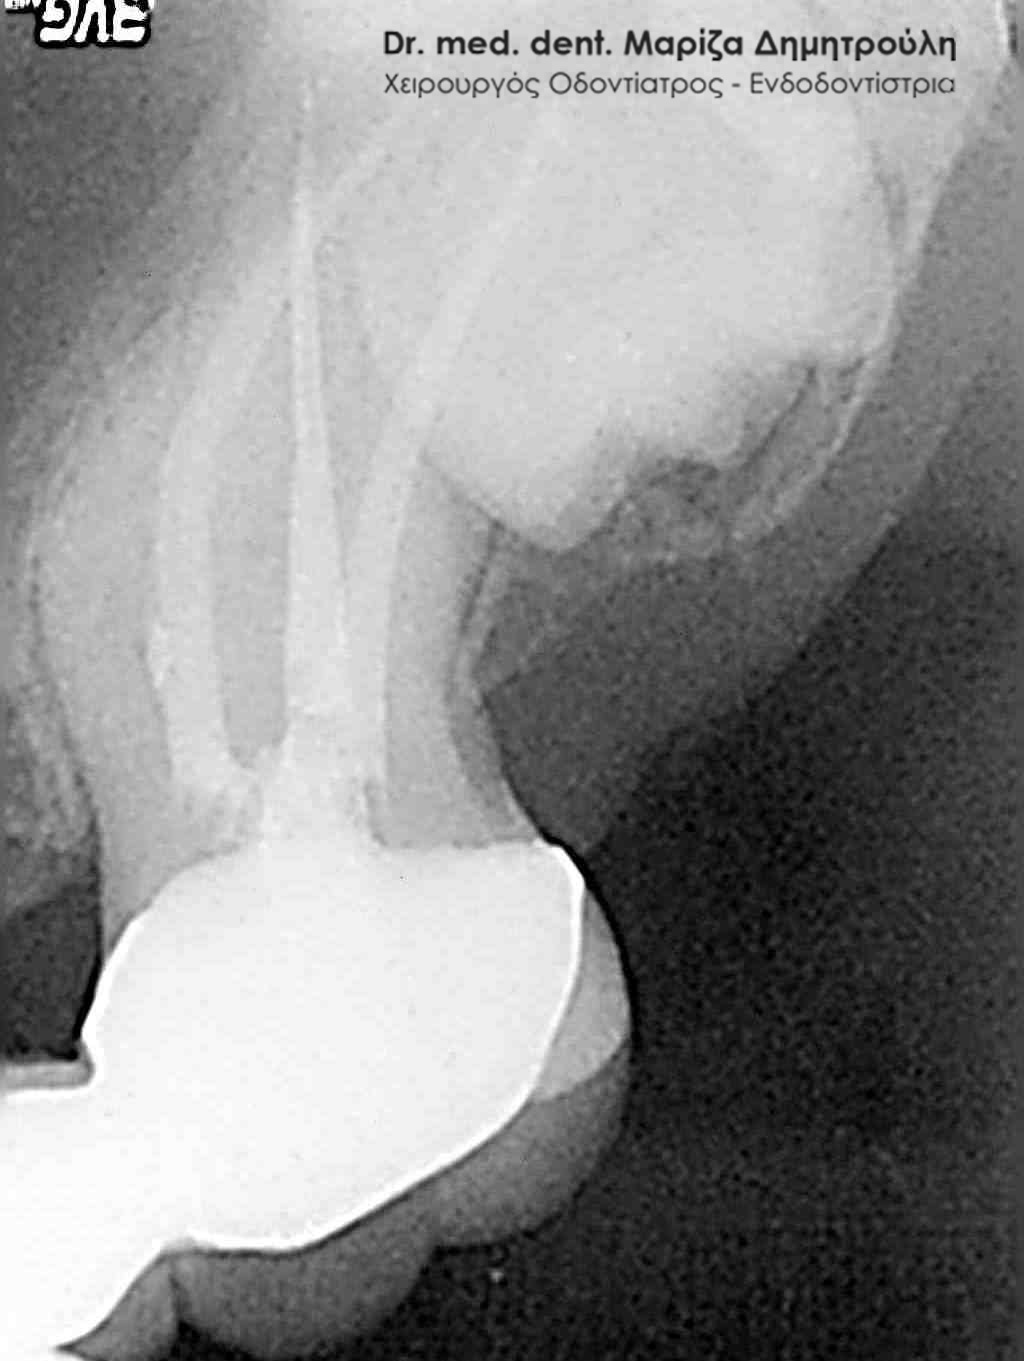

- με ενασβεστιωμένους ( κλειστούς ) ριζικούς σωλήνες

Οι ενδοδοντολόγοι είναι οδοντίατροι με περαιτέρω πανεπιστημιακή ειδίκευση, η οποία διαρκεί τουλάχιστον τρία χρόνια μετά την απόκτηση του πτυχίου του οδοντίατρου. Ο ενδοδοντιστής έχει ειδικευθεί στην απονεύρωση δοντιών με ασυνήθιστη μορφολογία, με στενούς ή έντονα κεκαμένους ριζικούς σωλήνες, κ.α., περιστατικά δηλαδή που συνήθως δεν μπορεί να αντιμετωπίσει ένας κοινός οδοντίατρος. Ο ενδοδοντιστής, σε σχέση με έναν κοινό οδοντίατρο, χρησιμοποιεί κατά τη διάρκεια της απονεύρωσης ειδικές τεχνικές, εξειδικευμένα εργαλεία και υλικά, αλλά και προηγμένο τεχνολογικό εξοπλισμό. Δεν είναι λίγες οι περιπτώσεις που ένας ενδοδοντολόγος έχει καταφέρει να “σώσει” δόντια, τα οποία από έναν κοινό οδοντίατρο είχαν καταδικαστεί σε εξαγωγή. Απαιτητικά περιστατικά για έναν ενδοδοντιστή χαρακτηρίζονται δόντια με ενασβεστιωμένους (κλειστούς) ριζικούς σωλήνες όπως και δόντια που απαιτούν επανάληψη ενδοδοντικής θεραπείας / απονεύρωσης (δόντια δηλαδή που είχαν ήδη απονευρωθεί στο παρελθόν και παρουσιάζουν εκ νέου φλεγμονή και ίσως αλλοίωση στο οστό).